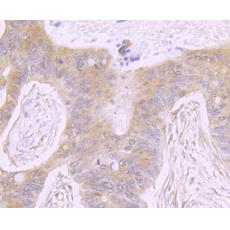

Fig5: Immunohistochemical analysis of paraffin-embedded human colon cancer tissue using anti-ATP citrate lyase antibody. Counter stained with hematoxylin.

Fig6: Immunohistochemical analysis of paraffin-embedded human pancreas tissue using anti-ATP citrate lyase antibody. Counter stained with hematoxylin.